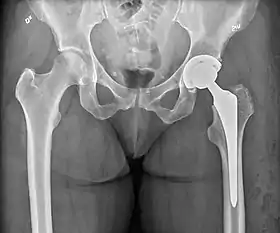

Hip prosthesis for hemiarthroplasty. This example is bipolar, meaning that the head has two separate articulations.

X-ray of the hips, with a right-sided hemiarthroplasty